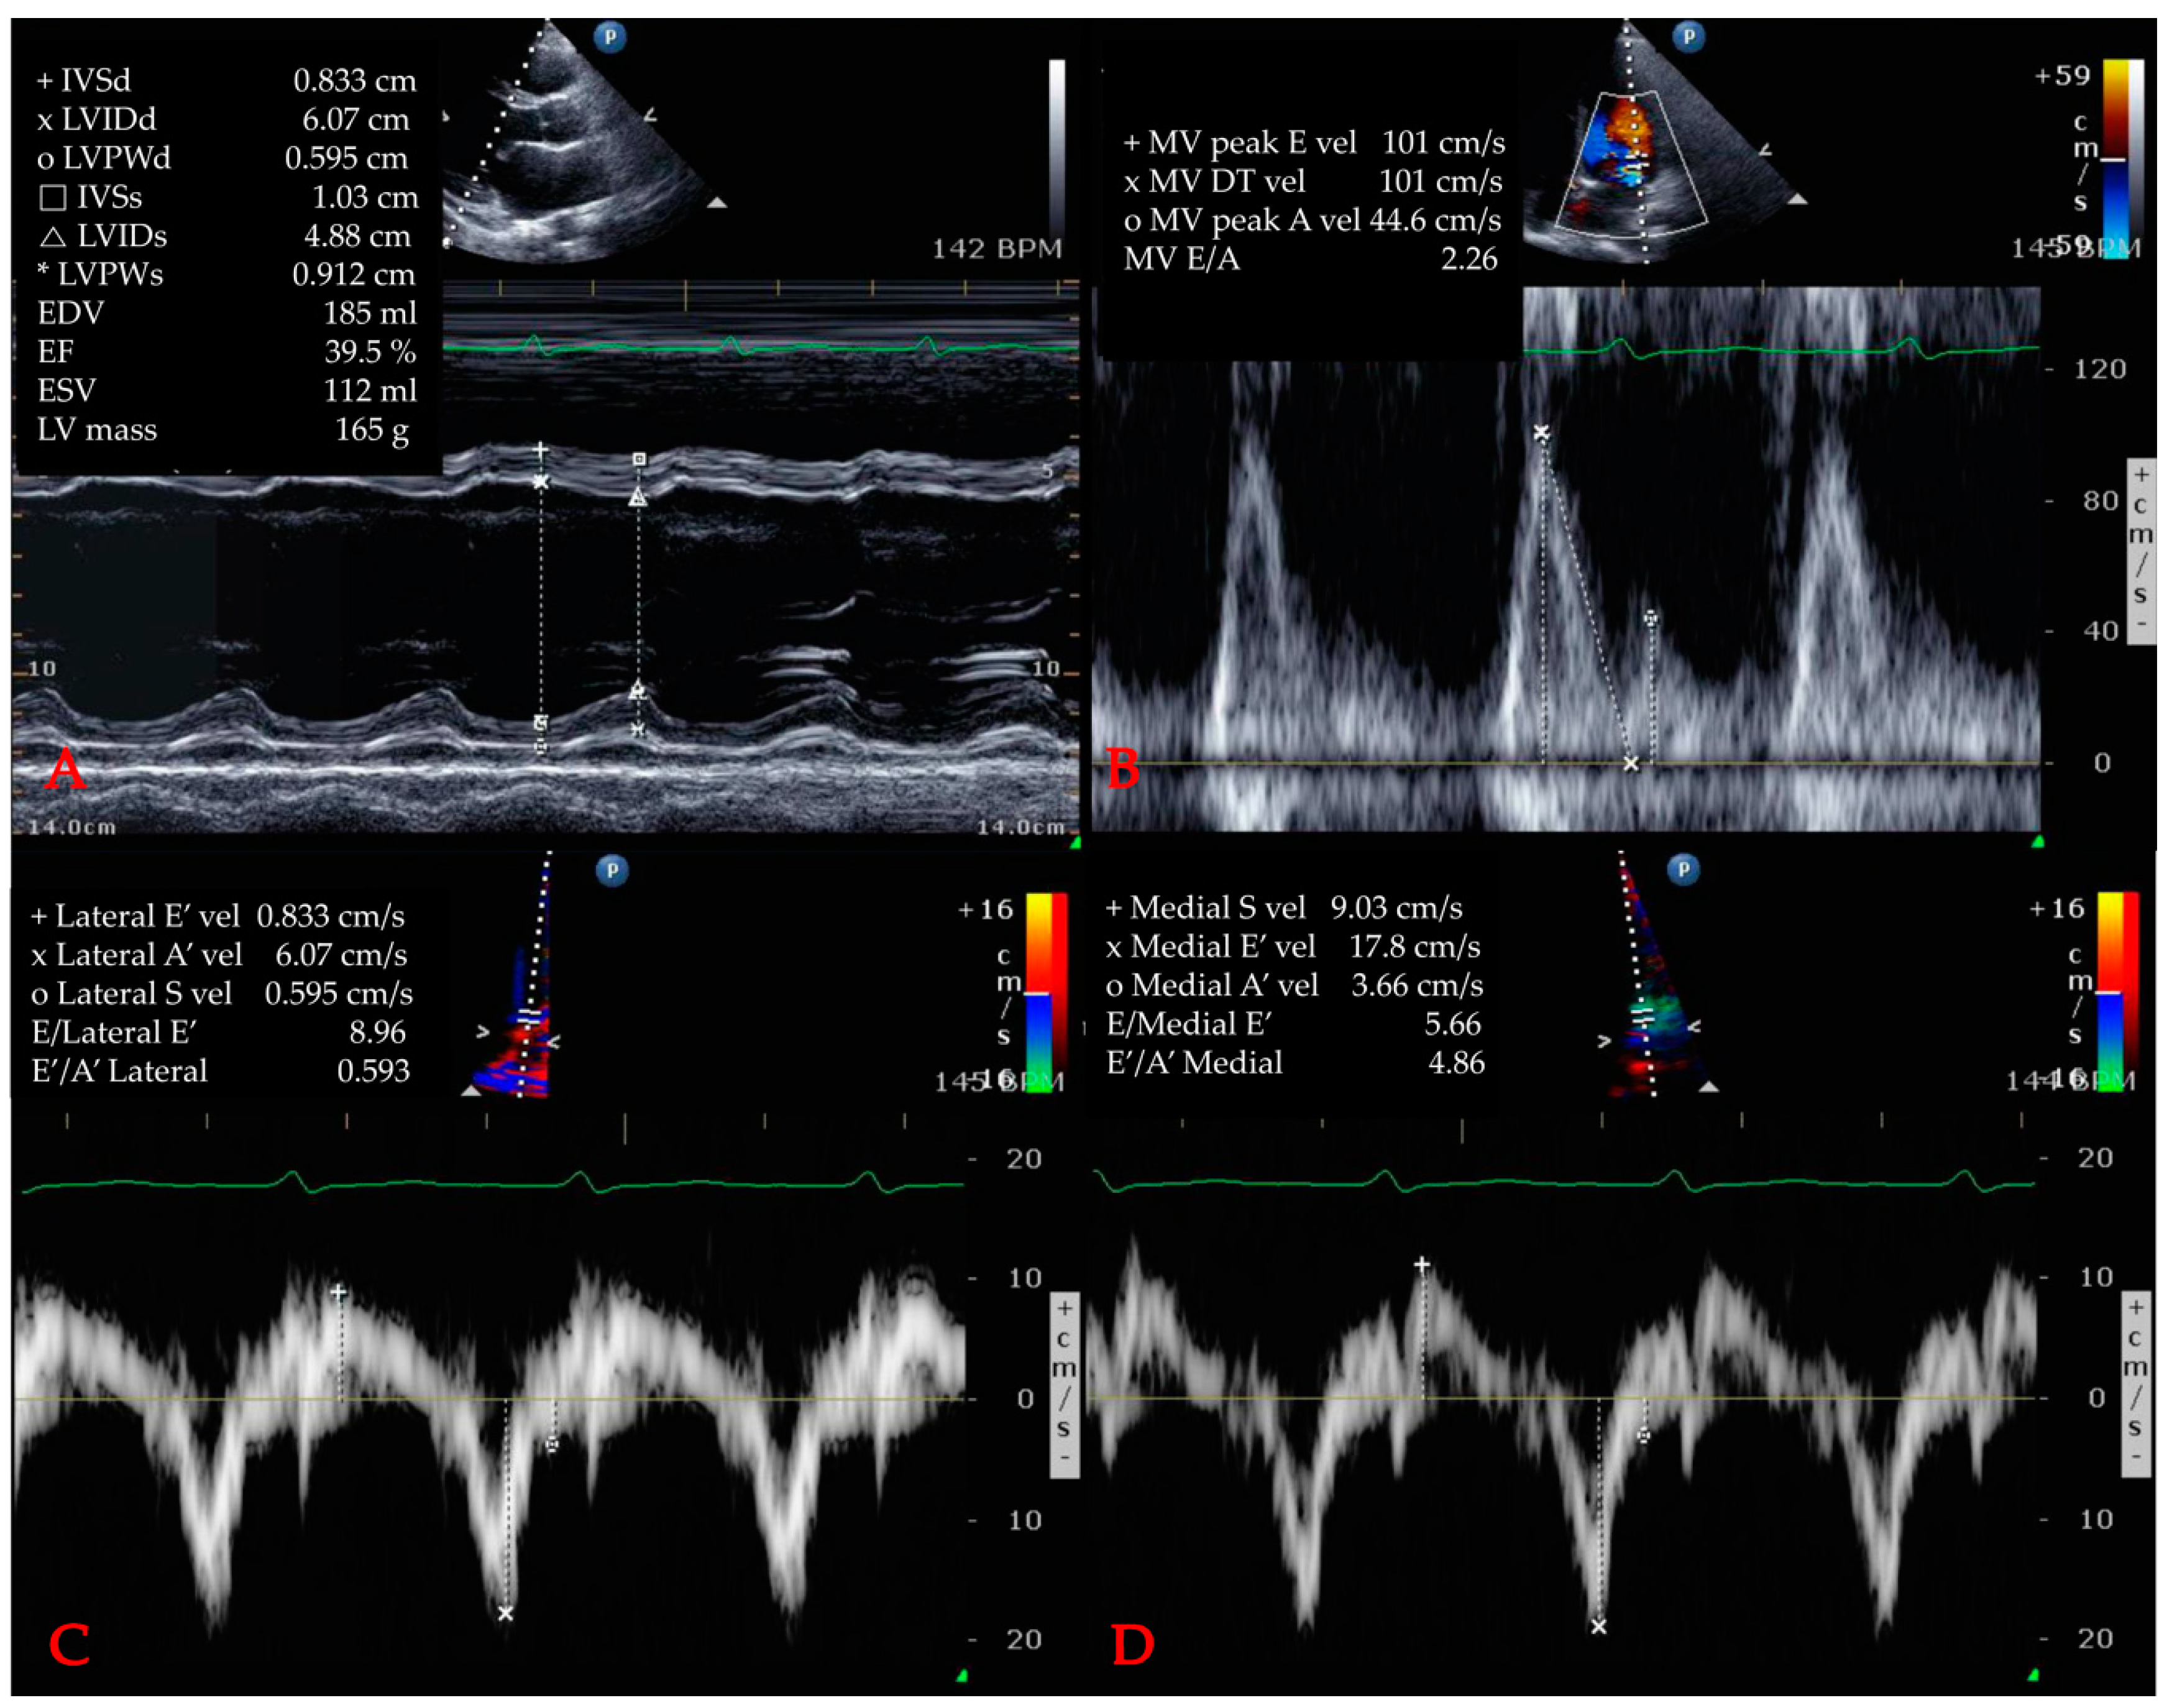

2.5. Echocardiographic Variables

| LVIDs (mm) | 33.0 (27.0–39.0) | 29.0 (25.0–33.0) | 35.0 (28.8–40.3) | <0.001 *** |

| LVIDd (mm) | 48.0 (42.3–52.0) | 45.5 (41.0–50.0) | 59.0 (44.0–54.0) | <0.001 *** |

| LVPWs (mm) | 13.0 (12.0–15.0) | 14.0 (12.3–15.0) | 13.0 (12.0–15.0) | <0.001 *** |

| ESV (mL) | 42.0 (28.0–66.0) | 31.5 (25.0–40.0) | 49.5 (33.0–74.0) | <0.001 *** |

| EDV (mL) | 90.0 (69.0–113.5) | 81.5 (66.3–97.8) | 98.5 (76.0–125.3) | <0.001 *** |

| IVSs (mm) | 13.0 (11.0–14.0) | 13.5 (12.0–15.0) | 13.0 (11.0–14.0) | <0.001 *** |

| IVSd (mm) | 9.0 (8.0–10.0) | 9.0 (8.0–10.0) | 9.0 (8.0–10.0) | 0.173 |

| LV mass (g) | 148.6 (114.5–175.6) | 144.8 (111.1–164.5) | 159.0 (128.6–189.2) | 0.029 * |

| LVEF (%) | 55.0 (40.0–62.0) | 61.0 (57.0–65.0) | 49.0 (35.0–59.0) | <0.001 *** |

| Peak E velocity (cm/s) | 69.0 (54.0–90.0) | 62.0 (52.0–77.8) | 69.0 (53.8–86.8) | 0.090 |

| Peak A velocity (cm/s) | 77.0 (62.0–92.0) | 75.0 (63.3–87.5) | 75.0 (59.0–93.0) | 0.111 |

| Deceleration time (ms) | 174.0 (140.0–213.0) | 199.0 (155.3–234.3) | 172.0 (139.5–207.5) | <0.001 *** |

| E/A ratio | 0.84 (0.65–1.13) | 0.87 (0.65–1.13) | 0.86 (0.72–1.21) | 0.707 |

| E/e’ ratio | 12.0 (9.0–15.0) | 10.0 (9.0–12.0) | 14.0 (10.0–17.0) | <0.001 *** |